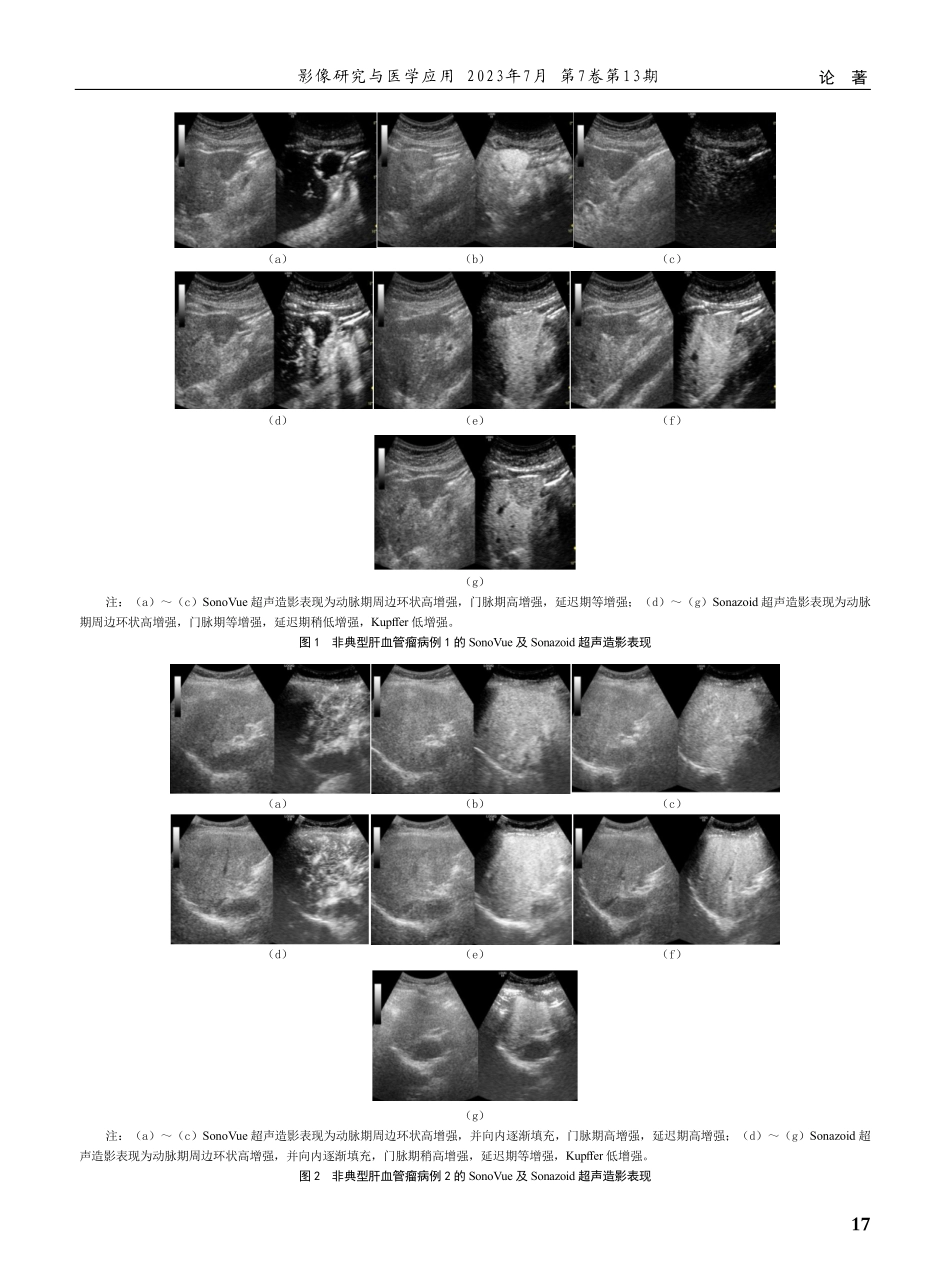

15论著影像研究与医学应用2023年7月第7卷第13期肝血管瘤是肝内最常见的良性病变,普通人群中的发生率约为7.3%[1],超声检查是临床重要的检查方法之一,具有典型超声表现者常规超声即可诊断。但部分肝血管瘤常合并有坏死、出血、血栓及瘢痕等,声像图表现复杂多变,与恶性肿瘤等占位性病变鉴别诊断困难,误诊率可高达50%~60%[2]。近年来,随着超声造影(contrast-enhancedultrasound,CEUS)技术逐渐应用于临床,已有研究证实CEUS可以明显提高肝血管瘤的诊断准确率、敏感性及特异性[3]。目前国内常规应用的超声造影剂为SonoVue,是一种血池造影剂,可以通过显示病灶内的微血管灌注对病灶的良恶性进行定性诊断。而Sonazoid是一种新型超声微泡造影剂,除了具备SonoVue的血池显像的特点外,还具有特异性的血管后期显像[4]优势,因此在肝脏局灶性病变的定性诊断中具有较高的价值。但目前国内对于Sonazoid和SonoVue在肝血管瘤中联合应用的研究报道尚少,因此本研究旨在对Sonazoid与SonoVue在肝血管瘤中的超声表现进行初步研究,探索其在临床诊断中的应用价值。1资料与方法1.1一般资料回顾性分析2020年1月—2022年12月于无锡市人Sonazoid与SonoVue超声造影在肝血管瘤诊断中的应用价值研究张雨1,吴鸣宇2,周锋盛1(通信作者)(1无锡市人民医院<南京医科大学无锡医学中心>超声医学科江苏无锡214023)(2无锡市人民医院<南京医科大学无锡医学中心>肝胆外科江苏无锡214023)【摘要】目的:探讨Sonazoid和SonoVue超声造影在肝血管瘤诊断中的应用价值。方法:回顾性分析2020年1月—2022年12月于无锡市人民医院就诊的肝血管瘤患者30例的超声及临床资料,分析肝血管瘤在两种超声造影剂下的灌注模式,在动脉期、门脉期、延迟期和血管后期(Kupffer期)的超声造影表现。以手术、穿刺病理或多种临床资料诊断结果为肝血管瘤为“金标准”,分别计算Sonazoid和SonoVue超声造影检查在肝血管瘤诊断中的准确率。结果:以手术、穿刺病理或多种临床资料诊断结果为肝血管瘤作为诊断“金标准”,Sonazoid和SonoVue超声造影诊断肝血管瘤的准确率分别为85.37%、80.49%。结论:Sonazoid和SonoVue超声造影对于肝血管瘤的诊断准确性无明显统计学差异,应用Sonazoid可以利用Kupffer相的增强特点来对病灶的良恶性进行进一步的鉴别诊断,但对于肝血管瘤的超声造影诊断,血管相仍然是诊断的重点。【关键词】超声造影;Sonazoid;SonoVue;肝脏血管瘤【中图分类号】R445.1【文献标识码...